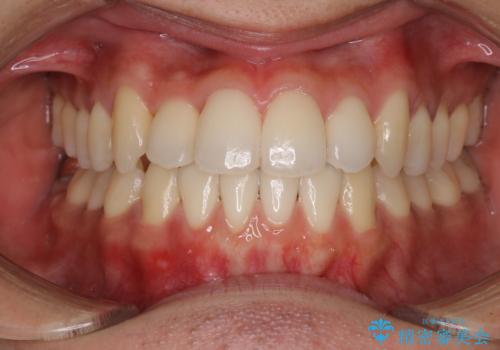

前歯のクロスバイトを短期間で解消 目立たないワイヤー矯正